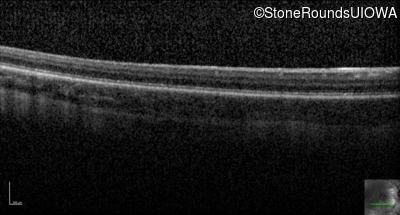

Optical Coherence Tomography - Right - 10/125

Exemplar